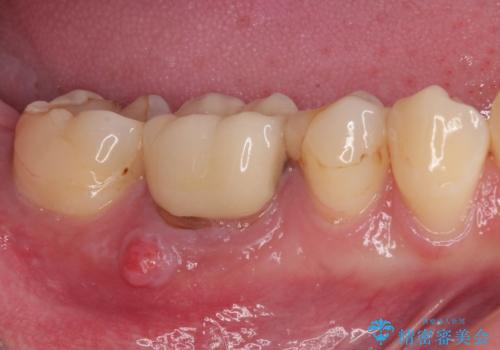

奥歯がしみる オールセラミッククラウンによる奥歯のむし歯治療